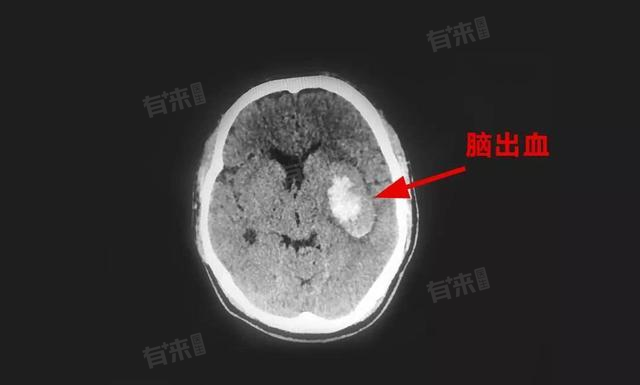

左侧基底节区脑出血成因与治疗,高血压致血管病变、血管畸形以及脑淀粉样血管病均可引发,治疗分内科与外科,术后还需康复促恢复以提患者生活质量。

- 高血压:长期高血压可使脑内小动脉发生玻璃样变、纤维素样坏死等病理改变,在血压波动时,这些病变血管易破裂出血,是左侧基底节区脑出血最常见原因。当血压急剧升高时,基底节区的豆纹动脉等承受较大压力,血管壁薄弱处首先破裂,导致出血发生。